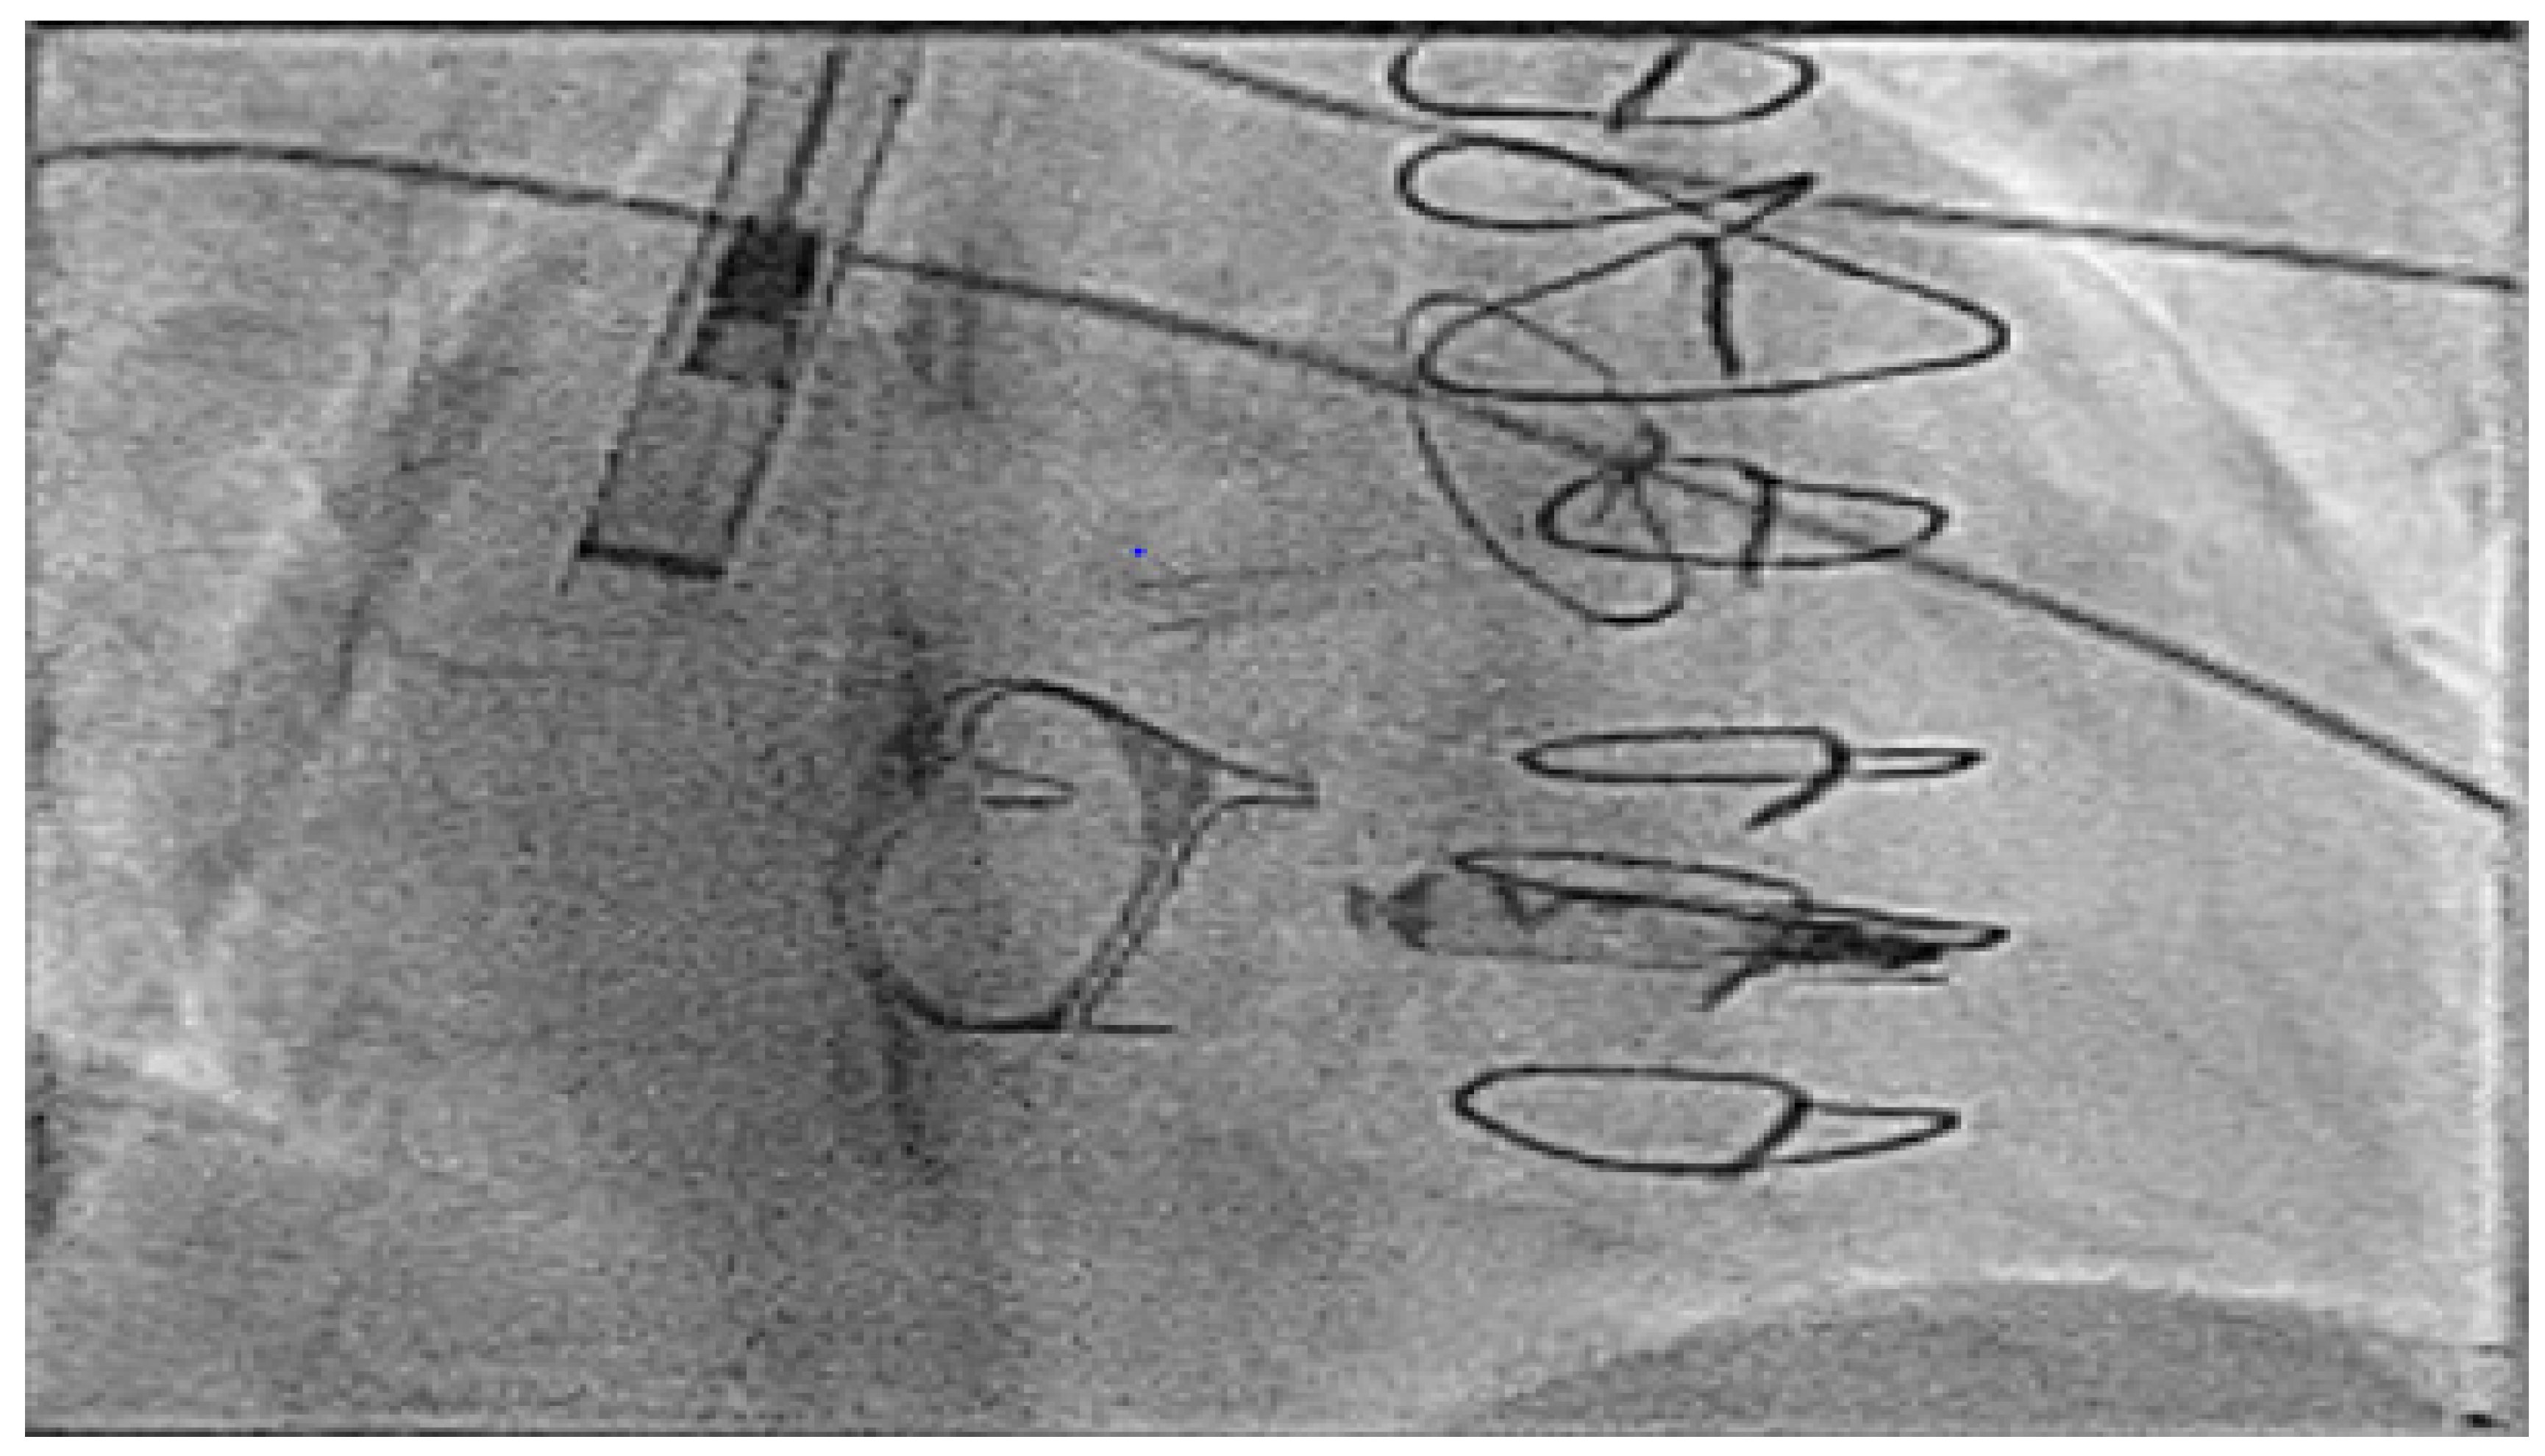

- Hayle, P.; Altayeb, F.; Hale, A.; Rao, A.; Ashrafi, R. Case report demonstrating novel approaches for leadless pacemaker implantation in the single ventricle heart. Eur. Heart J. Case Rep. 2025, 9, ytaf146. [Google Scholar] [CrossRef]

- Goulden, C.J.; Khanra, D.; Llewellyn, J.; Rao, A.; Evans, A.; Ashrafi, R. Novel approaches for leadless pacemaker implantation in the extra-cardiac Fontan cohort: Options to avoid leaded systems or epicardial pacing. J. Cardiovasc. Electrophysiol. 2023, 34, 2386–2392. [Google Scholar] [CrossRef]